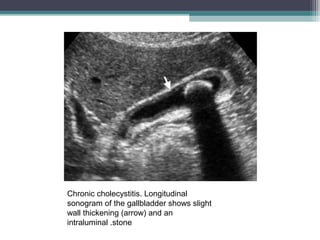

Chronic cholecystitis

• Refers to prolonged inflammatory condition that affects the gallbladder. It is almost

always seen in the setting of cholelithiasis (95%), caused by intermittent obstruction

of the cystic duct or infundibulum or dysmotility.

• IMAGING :

GB wall thickeningin the presence of gall stones

GB may appear normal in size or distended with gall stones

Chronic Cholecystitis can be differenciated from acute by the absence of

a)GB wall enhancement

b) Inceased transcient pericholecysitc hepatic enhancement

c) Pericholecystic inflammation

d) wall hyperemia

e) Murphy s sign

Chronic cholecystitis. Longitudinal

sonogram of the gallbladder shows slight

wall thickening (arrow) and an

intraluminal .stone

Chronic cholecystitis • Refersto prolonged inflammatory condition that affects the gallbladder. It is almost always seen in the setting of cholelithiasis (95%), caused by intermittent obstruction of the cystic duct or infundibulum or dysmotility. • IMAGING : GB wall thickeningin the presence of gall stones GB may appear normal in size or distended with gall stones Chronic Cholecystitis can be differenciated from acute by the absence of a)GB wall enhancement b) Inceased transcient pericholecysitc hepatic enhancement c) Pericholecystic inflammation d) wall hyperemia e) Murphy s sign

Chronic cholecystitis. Longitudinal sonogramof the gallbladder shows slight wall thickening (arrow) and an intraluminal .stone